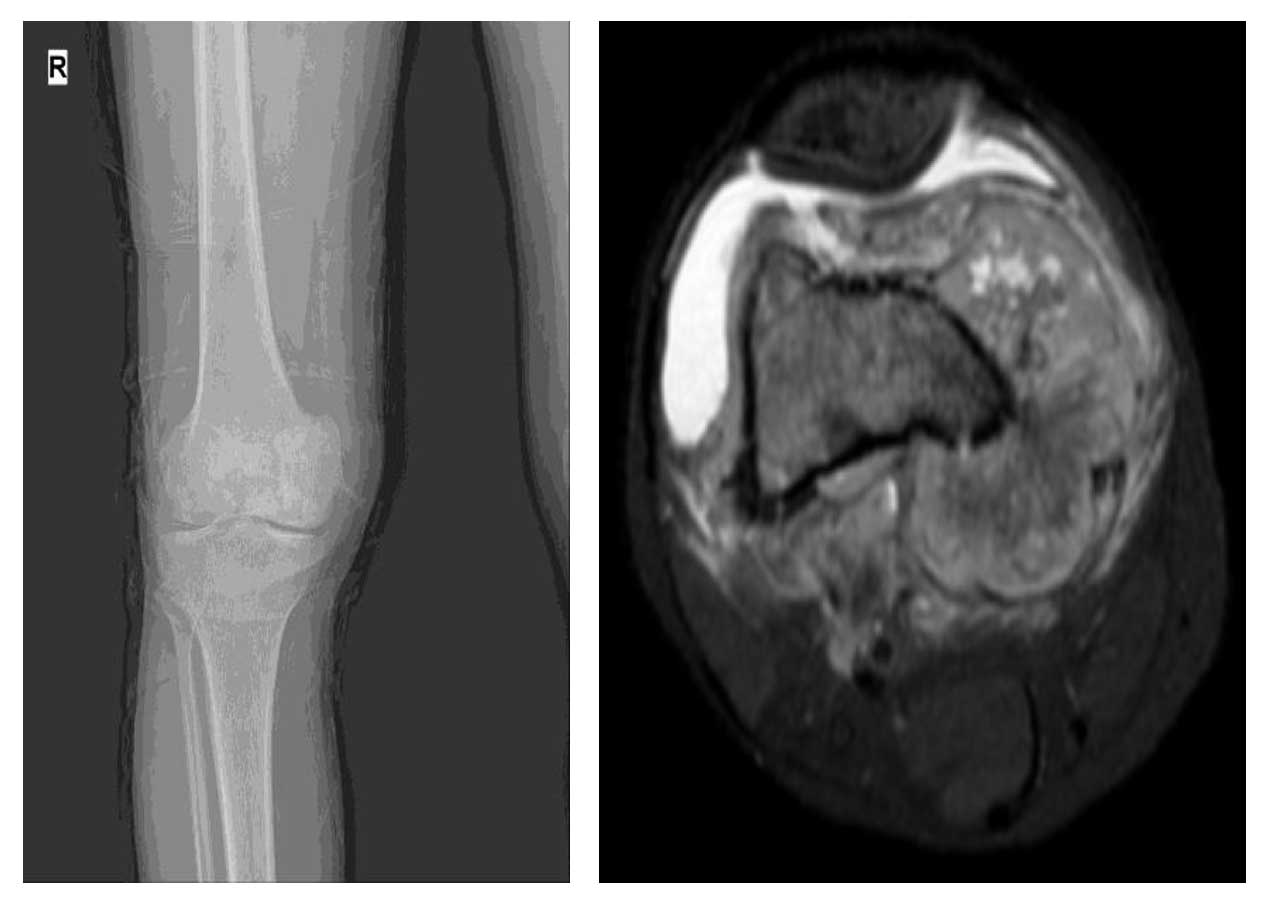

Ameliyat Öncesi: Röntgende distal femurda düzensizlik, MR’da aynı lokalizasyonda büyük tümör dokusunun eşlik ettiği eklemde efüzyon görülmekte.